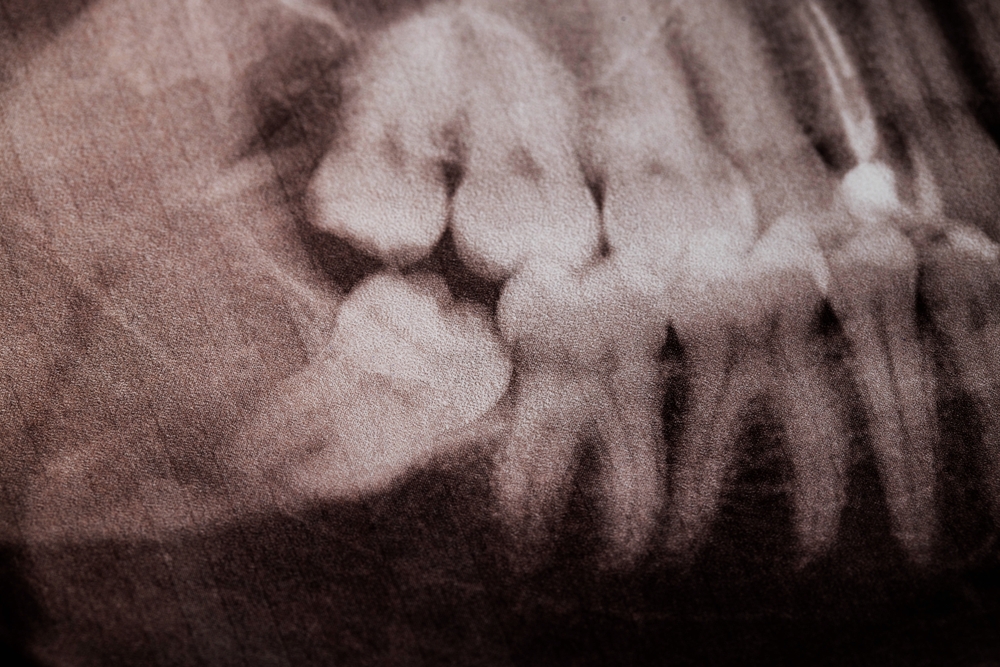

Not every child will need their wisdom teeth removed, which is why we focus on careful monitoring first. Using low-dose digital X‑rays and growth assessments, Dr. Cody evaluates:

• Tooth position and angulation (whether they are impacted or tilted)

• Effect on nearby teeth, roots, and developing bone